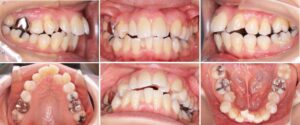

10才女子の症例です。

「歯並びがガタガタして気になる」「食事の時にうまく嚙み切る事ができない」と相談に来られました。

詳しく調べてみると、顎の位置も不安定で頭痛なども認められたため、まず顎の位置を安定させる装置(スプリント)を使って症状の緩和を図りました。

その後、矯正治療を行いました。

一期治療では、上下の顎の成長のコントロールと、右上犬歯の埋伏歯(顎の骨の中に埋まったまま生えてこない歯)が生えてくるためのサポートをしました。

二期治療では、開咬(噛んだ時の上下の前歯の隙間)と叢生(デコボコ)の状態を良くするために、上の歯の小臼歯を抜いて歯を並べるスペースを作りました。

そして歯並びを整えるためにワイヤーの装置や、顎に力をかけるパラタルバー、アンカースクリューを使いました。

矯正治療費用:一期治療 ¥420,000 二期治療 ¥432,000

矯正治療期間:一期治療 3年10ヶ月 二期治療 2年10ヶ月

矯正治療回数:一期治療 14回 二期治療 15回

治療前

一期治療中

二期治療中

治療後